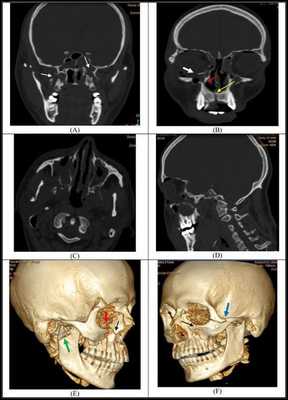

Симптоматика переломов костей средней зоны лица многообразна, поэтому для постановки точного диагноза требуется выполнение рентгенологической диагностики. Самым современным и точным методом является компьютерная томография . С её помощью челюстно-лицевой хирург имеет возможность точно определить локализацию линии разъединения костных фрагментов и тип перелома, выбрать наиболее адекватную и малотравматичную тактику лечения [11] .

Отличительные признаки каждого типа проявляются по уровню подвижности фрагментов, тяжести состояния больного и данным дополнительных методов исследования (компьютерной томографии).